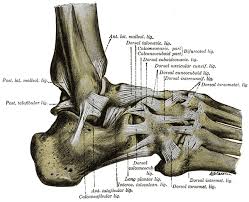

Andere Erkrankungen der Füße entstehen durch Krankheiten die viele Bereiche des Körpers betreffen wie Diabetes mellitus Gicht oder andere Arthritisformen. Die Knochen des Fußskeletts werden durch zahlreiche Bänder zusammengehalten und sind durch Gelenke miteinander verbunden. Alle von diesen Cookies erfassten Informationen werden aggregiert und sind deshalb anonym.

Den gesamten Komplex bilden außerdem Gelenke Fußwurzelgelenke Gelenke der Mittelfußknochen und Zehengelenke viele für die. Eine weitere Ursache für Schmerzen an der Fußaußenseite ist die Fraktur des fünften Mittelfußknochens. Der menschliche Fuß besteht aus 26 Knochen.